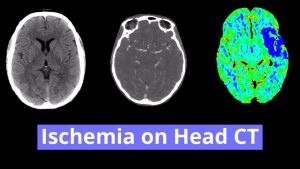

- No definite areas of loss of gray-white differentiation

- Patchy subcortical and periventricular white matter hypoattenuation

- Acute right MCA territory infarct (dense vessel sign)

Focal hyperdensity associated with an M2 branch of the right MCA concerning for age-indeterminate thrombus. Consider CTA for further evaluation. No definite CT findings of infarct; however, MRI is more sensitive for acute ischemia.

Sequela of chronic microvascular ischemic disease. Intracranial atherosclerosis.